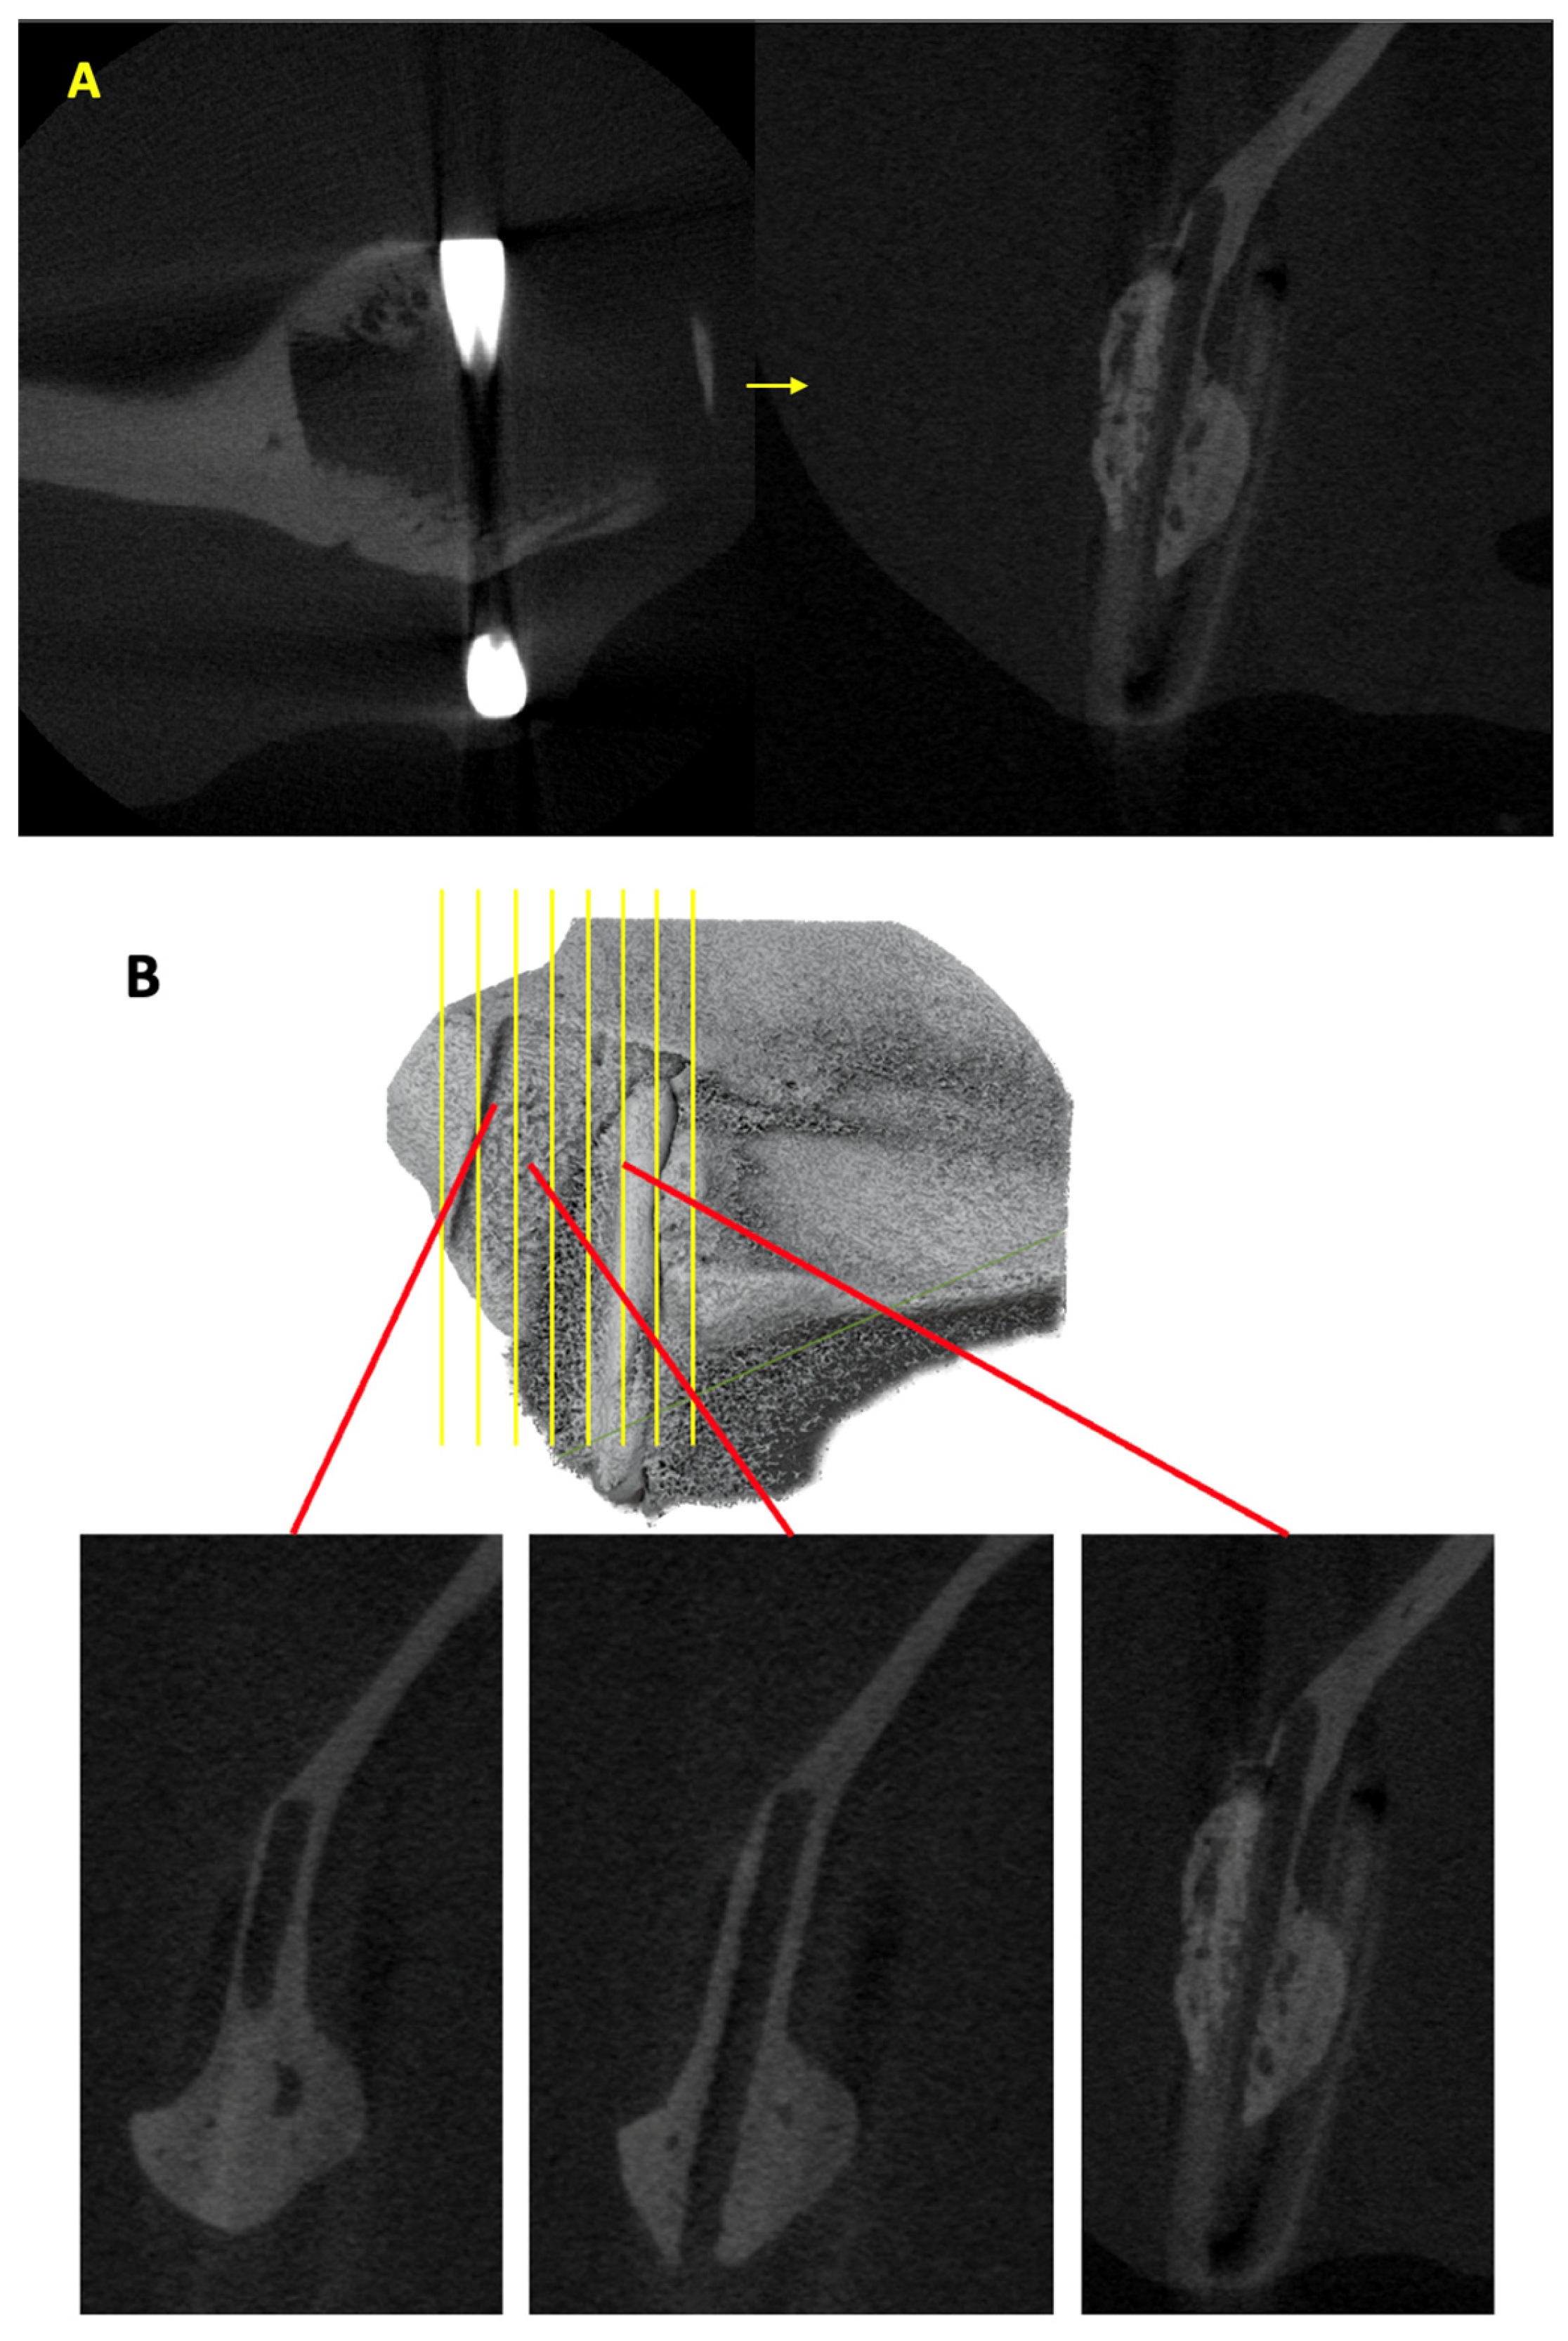

The scanned images of each specimen were analyzed using the ImageJ software (Fiji, version 2.14.0/1.54f) to evaluate the amount of new bone growth outside the material sheet. The two-dimensional (2D) images opened using ImageJ were initially displayed in the axial view. We used a specific rotation plugin, TransformJ, to enable the viewing of 2D images in the sagittal plane (Figure 5A). In the sagittal view, the cross-sections clearly indicated the material sheet location, host bone, new bone outside the sheet, and hemoclip (Figure 5B). Only the third-generation material sheet, u-HA/PLLA, was visually discernible in the micro-CT section because of the higher concentration of u-HA. We manually traced the new bone on the outer side of the sheet in each slice using the ‘Polygonal selection tool.’ The traced region was saved with the ‘Region of Interest (ROI) Manager’ tool. After measurement of the entire specimen, the individual areas marked were measured using the ‘Measure’ option in the ROI manager. The cumulative area was then calculated (Figure 5C). The total new bone volume was estimated with the formula V = ∑Si × d, where V is the volume in mm3; Si, the new bone area in a single micro-CT slice in mm2; and d, the thickness of one micro-CT slice (0.02 mm) [25].

Figure 5.

(A) Rotation of the section using the ImageJ plugin ‘TransformJ’ to view the image in the sagittal plane. Host bone, material relation to host bone, and newly formed bone can be differentiated clearly when viewed from the sagittal plane. (B) Sagittal images show newly formed bone on the outer aspect of the material sheet from the anterior to the posterior region in ImageJ. (C) Tracing the area of new bone from each slide using a polygonal selection tool and measuring the new bone area using ROI Manager in ImageJ.